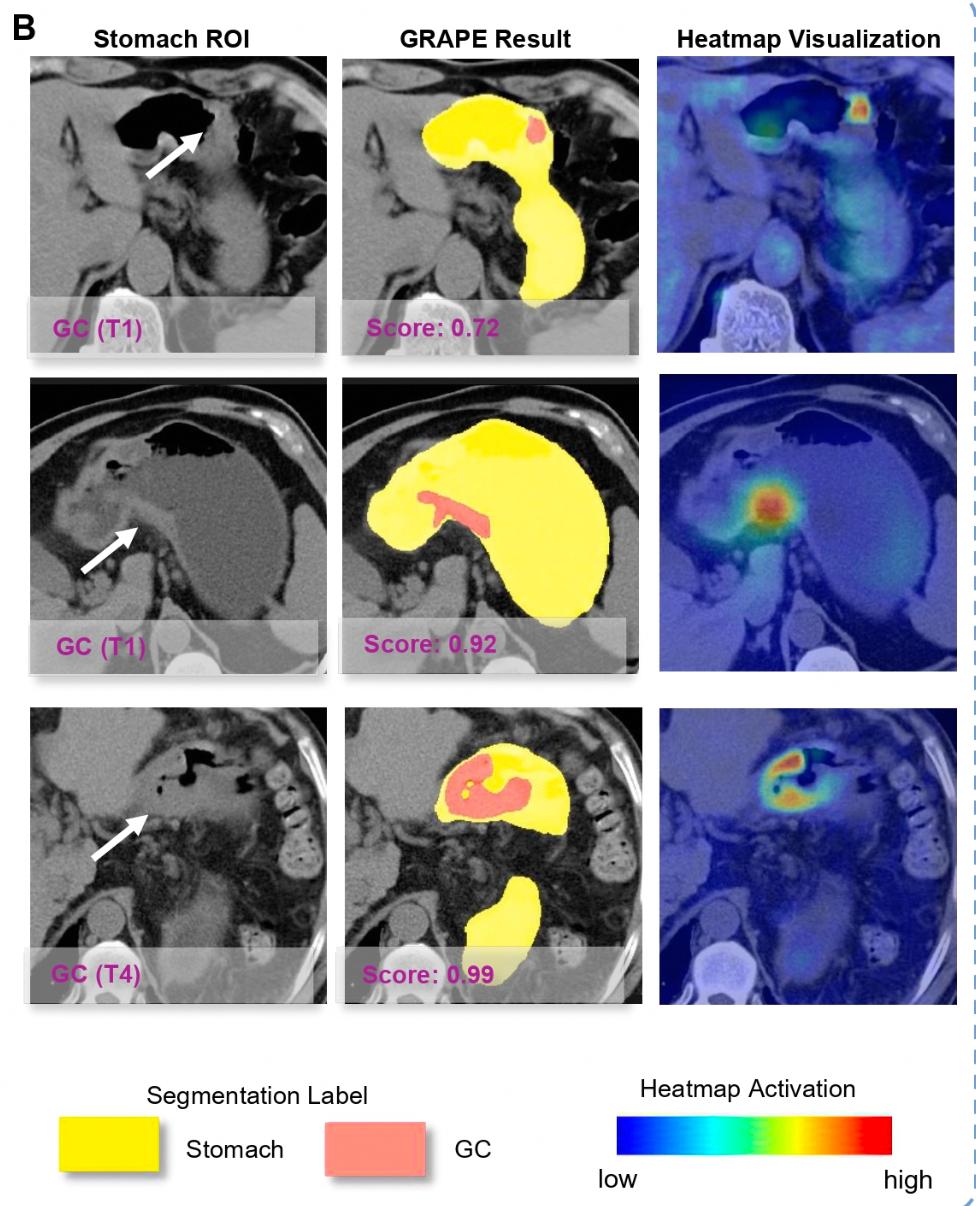

联队并未受到传统认知的束缚,相继克服了胃形变化大、内容物影响大、初期疾病局限于粘膜层等挑战,建立了世界上最大的胃癌扫描CT图像多中心数据(6720例),然后在此基础上开发AI模型DAMOO GRAPE。

DAMO 与人类放射科医生相比,GRAPE的敏感性和特异性分别达到85.1%和96.8%,分别增加21.8%和14.0%。

该AI模型具体应用于“平扫CT” AI在临床医学模式上,首先用AI对腹部平扫CT进行初步筛查,然后通过胃镜对AI提示的胃癌高危人群进行诊断。